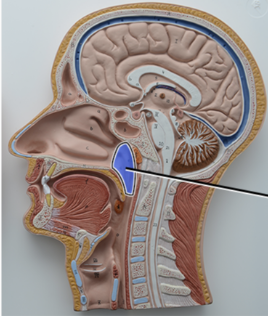

What structure is this?

Diaphragm

What structure is this?

Hard Palate

What structure is this?

Soft Palate

What structure is this?

Uvula

What structure is this?

Nasal cavity

What structure is this?

Superior Nasal Concha

What structure is this?

Middle Nasal Concha

What structure is this?

Inferior Nasal Concha

What structure is this?

The nasopharynx region of the pharynx

What structure is this?

The Oropharynx region of the pharynx

What structure is this?

The Laryngopharynx region of the pharynx

What structure is this?

Thyroid Cartilage

Nasal Septum